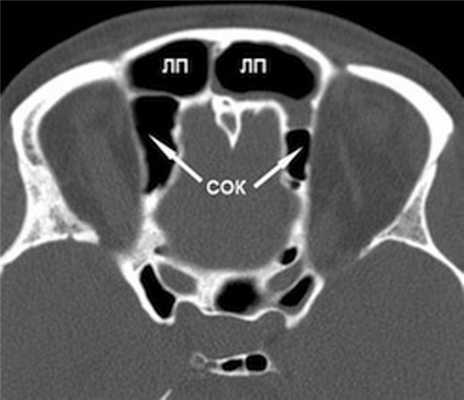

(Слева) На корональной КЛКТ (реконструкция) визуализируется добавочное переднее устье.

(Справа) На корональной КЛКТ визуализируются добавочные устья В, расположенные за основными. Картина сопоставима с таковой после хирургического вмешательства по поводу хронического синусита. Определяется утолщение слизистой оболочки В обеих верхнечелюстных пазух, обусловленное хроническим воспалением.